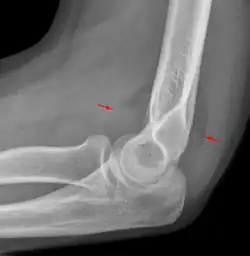

Anterior sail signs as well as posterior fat pad in a child with a supracondylar fracture.